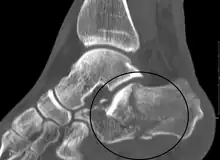

A fractured calcaneus as seen on CT

Conventional radiography is usually the initial assessment tool when a calcaneal fracture is suspected. Recommended x-ray views are (a) axial, (b) anteroposterior, (c) oblique and (d) views with dorsiflexion and internal rotation of the foot. However, conventional radiography is limited for visualization of calcaneal anatomy, especially at the subtalar joint. A CT scan is currently the imaging study of choice for evaluating calcaneal injury and has substituted conventional radiography in the classification of calcaneal fractures.[12] Axial and coronal views are obtained for proper visualization of the calcaneus, subtalar, calcaneocuboid and talonavicular joints.